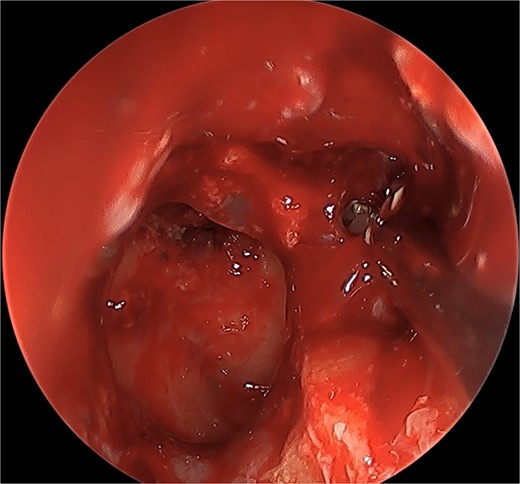

We present a case of a 52-year-old female, not known to have any chronic disease, who presented to our institution’s otorhinolaryngology clinic with a complaint of headache, facial pain, and PND for 6 months. Endonasal endoscopic examination was unremarkable. A paranasal sinus CT was requested to aid the diagnosis, which showed two simultaneous opacities occupying the left maxillary and right sphenoid sinuses, respectively (Fig. 1A and B). The opacified lesions were associated with calcifications, metallic shadowing, and bony thickening of the sinus wall. According to the history and radiological imaging findings, a diagnosis of a fungal ball occupying both the maxillary and sphenoid sinuses was achieved, and a functional endoscopic sinus surgery (FESS) with left wide maxillary antrostomy removal of the thick fungal debris occupying the left maxillary sinus (Fig. 2) was decided to be performed. In addition, a wide endoscopic sphenoidotomy was performed, and the sphenoid sinus was full of fungal debris (Fig. 3), which was cleaned thoroughly. The patient had an uneventful post-operative course.

Endoscopic view of simultaneous occurrence of the fungal ball in maxillary and sphenoid sinuses.

Post-operative endoscopic view post sphenoidectomy and maxillary antrostomy.